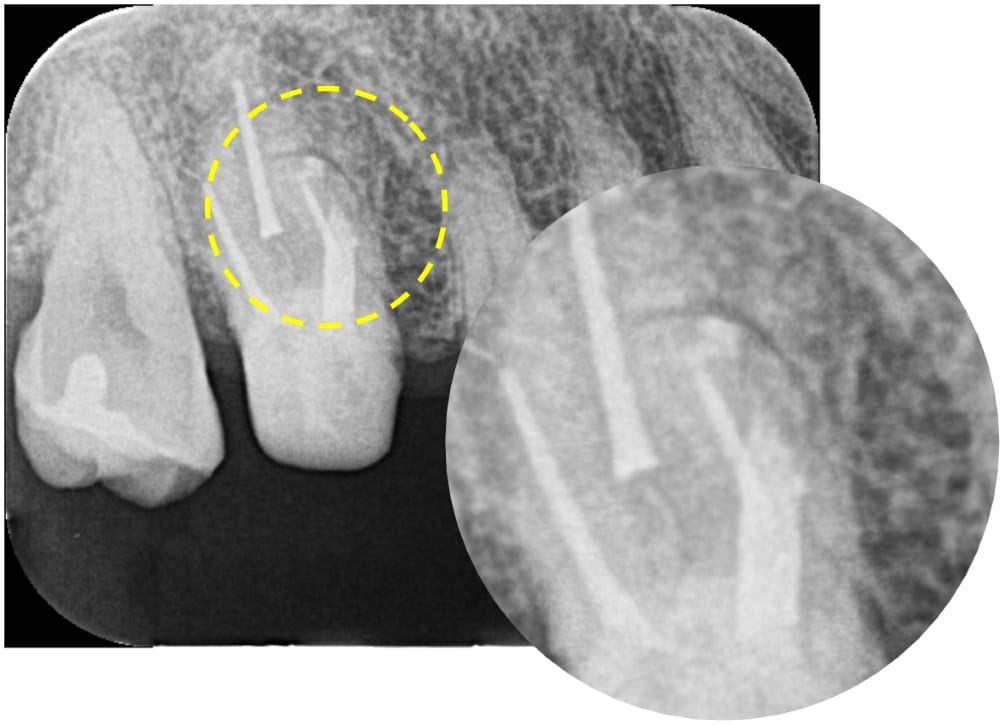

根管充填に使用するガッタパーチャポイントの到達位置の確認です。未処置であった他の根管も、根の先端付近まで器具が届いているのが確認できます。

破折ファイル除去とパーフォレーションリペアを行った後に、根管充填まで完了しました。

根の先にハッキリと写っていた黒い影も、術後12ヶ月では完全に消失し、治癒傾向を示しています。